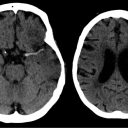

Na Univerzitetnem kliničnem centru (UKC) Ljubljana je potekala mednarodna konferenca “Brain Tumors: From...